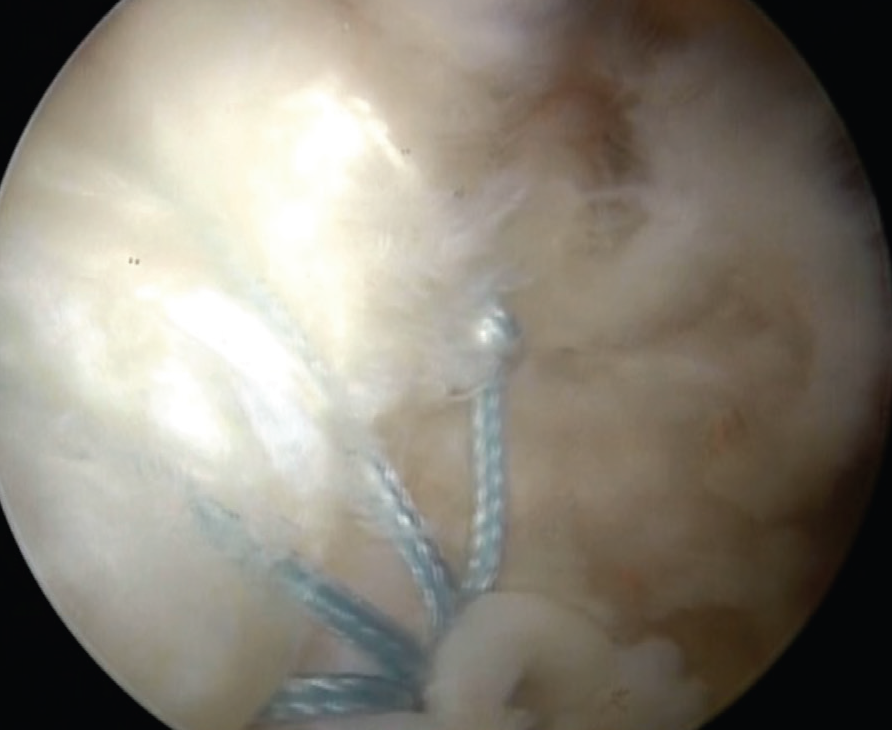

Artroskopik Tendon Onarımı: Bu işlemde, yırtık tendon kemiğe kamera (artroskop) yardımıyla ve küçük kesilerden el aletleri sokularak tespit edilir. Artroskopik cerrahide kamera sistemi ile elde edilen görüntüler yüksek kalite ve çözünürlükte olduğu için açık ameliyatta görülemeyen tüm detaylar monitörden izlenebilir.

![]() |

| A. Rotator manşet yırtığının artroskopik görüntüsü, B. Yırtığın artroskopik tamiri | |